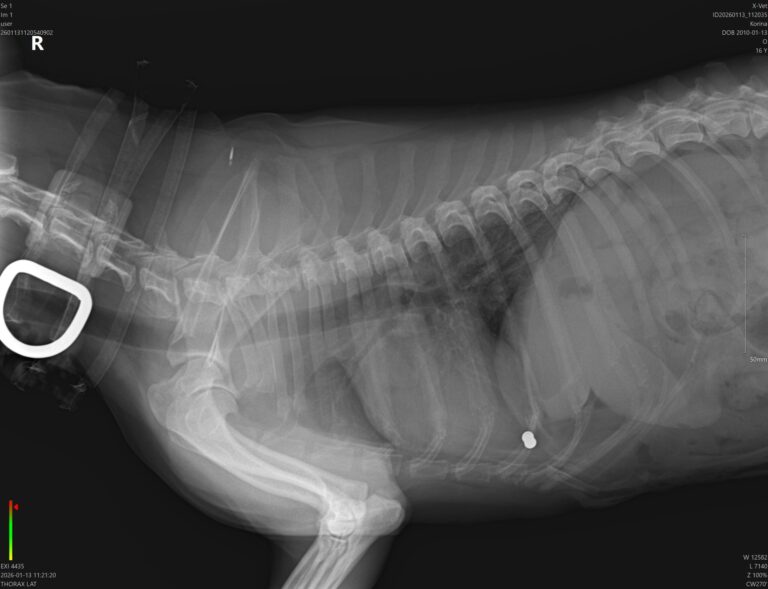

Pri príjme však pán doktor nahmatal 3 nádorčeky na mliečnej lište – častý problém u nekastrovaných sučiek vo vyššom veku. Predoperačné vyšetrenia dopadli však dobre, krv v norme, pľúca čisté, srdiečko bez problémov.

10.01.2026 Prebrali sme tri sučky po zosnulej majiteľke. Korina je z nich najstaršia, no pani ju našla a zachránila len nedávno, cca pred 4 mesiacmi. O nepeknej minulosti svedčí brok v tele… Čaká ju veterinárne ošetrenie, na mliečnej lište má 3 hrčky, ktoré budú musieť von a aj zuby sú v zlom stave a bude treba ich poriešiť…